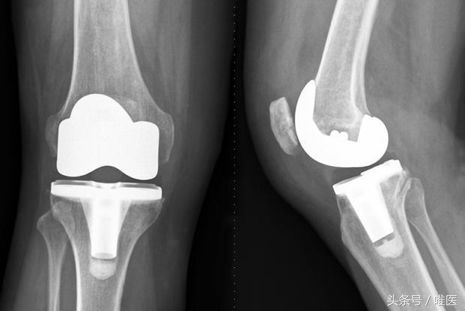

早期的膝关节骨关节炎,可以通过药物治疗,物理康复治疗等方法缓解,中晚期的膝关节骨性关节炎,保守治疗通常难以得到满意的效果,尤其是晚期的骨关节炎,从X线片上就能发现明显的病变。严重程度不同的骨关节炎,治疗的方法是不一样的,并不是所有的骨关节炎都需要手术治疗,同样,也并非所有的骨关节炎都可以通过药物控制。比如下面同一个病人的两个膝关节,病变处在不同的阶段,接受的治疗也不一样。

x线下两个膝关节的病变轻重明显不同

在临床中,总有一部分患者对于上述的保守治疗效果都不理想,这个时候,我们就需要通过手术来帮助他们解决问题。对于晚期的严重的膝关节骨关节炎而言,我们通常需要实行人工全膝关节置换术来帮助这些患者。人工全膝关节置换术是上个世纪出现的手术,也是现代骨科发展史上最为成功的手术之一,它能非常有效地根除晚期膝关节病痛,极大地提高病人的生活质量。目前,我国的人工全膝关节置换术开展已越来越普遍,成为了治疗晚期膝关节骨性关节炎的首选方法。

简单的说,这一手术就是将病变严重的膝关节股骨一侧和胫骨一侧的软骨和部分骨质以特殊的工具去除,然后根据每一个患者的膝关节尺寸选择合适型号的假体,用一种叫做骨水泥的粘合剂固定在膝关节内。通过这种手术,患者可以很快的正常行走和进行日常生活工作。